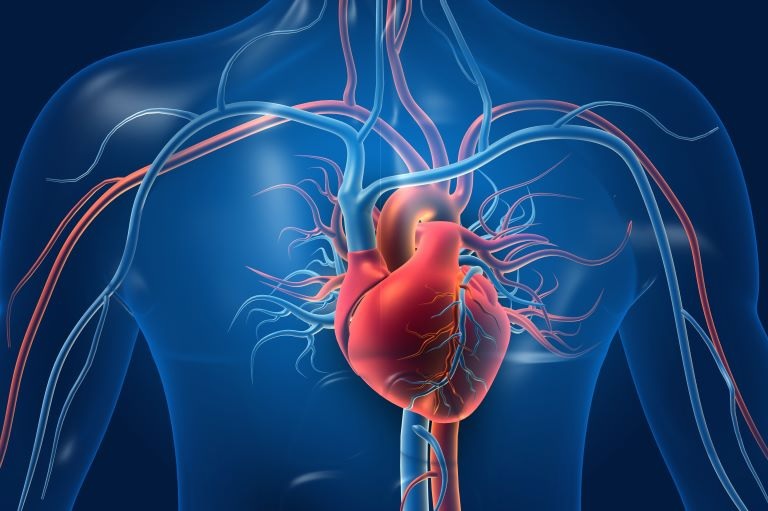

El corazón

Los beneficios que ofrece la vitamina C para la salud del corazón están relacionados con su función antioxidante. Al evitar la acumulación de radicales libres potencialmente dañinos, la vitamina C ayuda a proteger las células endoteliales, las cuales son una capa de células que recubre los vasos sanguíneos.2 Estas células tienen la importante tarea de regular el intercambio de oxígeno y nutrientes entre el torrente sanguíneo y los tejidos a su alrededor.

También se ha demostrado que la vitamina C aumenta las cantidades de un compuesto llamado tetrahidrobiopterina, el cual es necesario para la actividad de una enzima que produce óxido nítrico, un potente vasodilatador (un compuesto que abre o expande los vasos sanguíneos). A medida que aumentan los niveles de tetrahidrobiopterina, aumenta la producción de óxido nítrico. Esto es beneficioso, ya que permite que la sangre fluya más fácilmente a través de los vasos sanguíneos y asegura que el oxígeno y los nutrientes que se transportan en la sangre sean llevados de forma eficaz por todo el cuerpo. Las acciones vasodilatadoras del óxido nítrico también son importantes en la regulación de la presión arterial.3